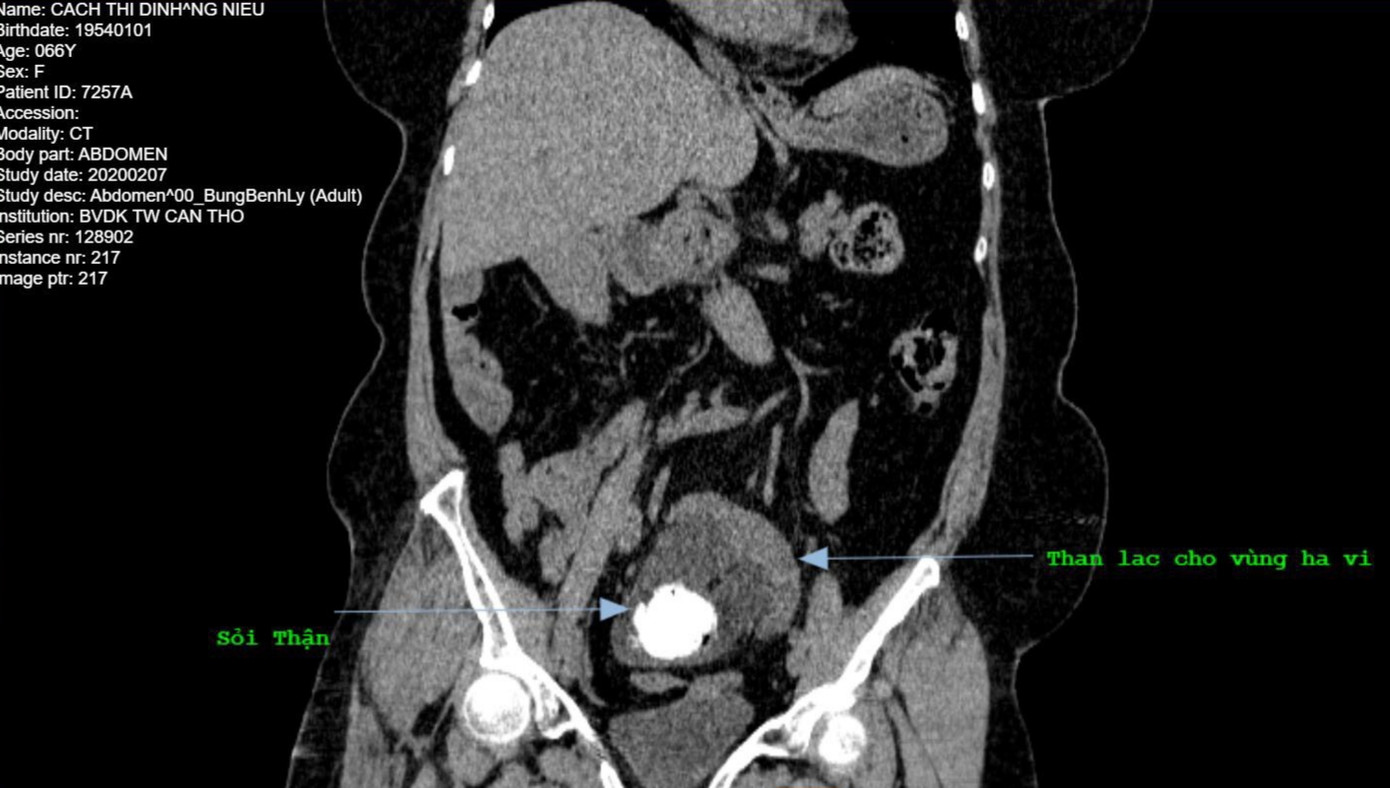

Phẫu thuật thành công cho người phụ nữ có thận nằm ở vị trí lạ ảnh 1Vị trí thận nằm lạc chỗ trong hố chậu.

Sau khi tiếp nhận bệnh nhân, các bác sĩ đã tiến hành siêu âm và chụp CT-scan. Kết quả cho thấy, bà Định có sỏi thận trái và đặc biệt là vị trí của thận trái lại nằm lạc chỗ trên vùng hố chậu, bên trong còn có có dịch kém thuần trạng. Bên cạnh đó, bệnh nhân này còn có bệnh lý đái tháo đường type 2, tăng  huyết áp, thiếu máu cục bộ cơ tim.

Nhận định đây là một trường hợp đặc biệt, bệnh nhân được chỉ định phẫu thuật lấy sỏi thận trái. Ngay sau đó, ekip phẫu thuật đã tiến hành mổ thận trái và lấy ra viên sỏi to, kích thước 33x27mm và bơm rửa ra nhiều sỏi bùn.